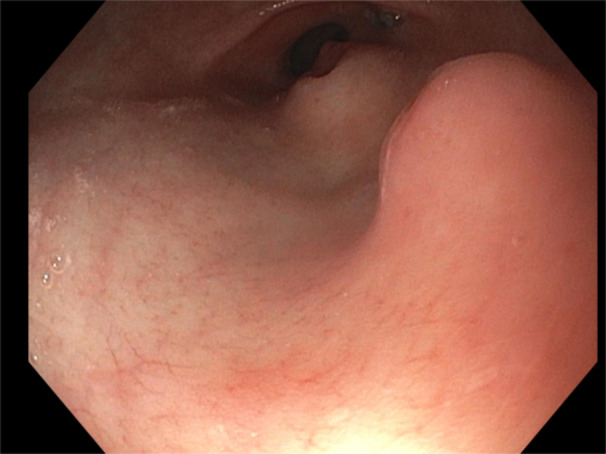

A 13-year-old with dual pancreatic rests.